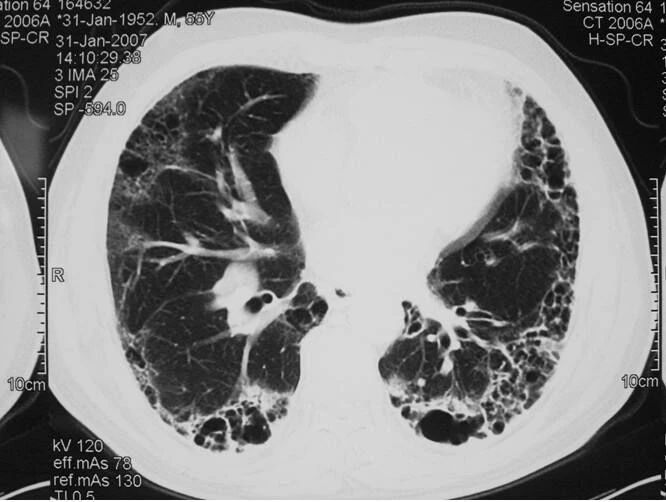

下图是同一位患者三次CT检查的图像,每次检查相隔2天,我们来看看肺部的变化。

大家可以很清楚地看到,右侧(患者的左胸)肺部全变白了,左侧(患者右胸)变白的面积也是非常大。

正常的肺组织里含有大量的空气,对X线的阻挡能力很弱,所以在X线下呈现黑色。当肺部出现炎症反应,大量蛋白、组织液、白细胞等渗出,肺间质充血、水肿等,这时的肺组织对X线的吸收能力就明显增强了,有点像实质器官的表现,所以呈现出白色。

变成白色的肺组织,基本上失去了气体交换的能力,患者会感到明显的缺氧,呼吸困难。我们需要给患者吸氧,重症者上呼吸机,甚至动用ECMO进行治疗。上面我举例的这位患者,就是一位新型冠状病毒感染的患者,最终由于病情发展太快,而不幸死亡。